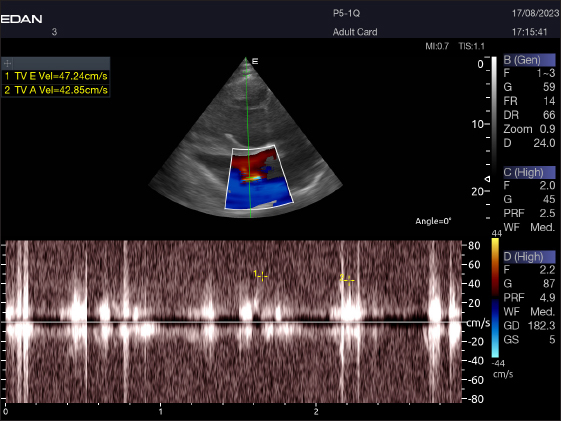

Fig. 9. Left parasternal longitudinal axis of an 18-year-old racing camel showing pulsed wave Doppler over the tricuspid valve (1=E wave and 2=A wave).

The Mv E/A (Fig. 8), Tv E/A (Fig. 9), and maximum velocity of the aortic valve (Av Vmax) (Fig. 10) were all measured using pulsed-wave Doppler at LPSLAx in all camels. Two cases were observed with mild mitral regurgitation detected through continuous-wave Doppler, but the regurgitation was not considered significant (Fig. 11).

Table 4 provides an overview of pulsed-wave Doppler echocardiographic serial measures in adult racing camels. The pulsed-wave Doppler echocardiographic measurements’ mean values ± standard deviation were recorded for Tv E/A (1.3 ± 0.2 cm2), Mv E/A (1.3 ± 0.2 cm2), Av max (−88.2 ± 25.1 cm/second), and Pv max (−59.2467 ± 17.4 cm/second), as shown in Table 4.

The pulsed-wave Doppler echocardiography of racing camels is not well documented. While all camels had their Mv E/A, Tv E/A, and maximum velocity of the Av Vmax recorded using pulsed-wave Doppler at (LPSLAx), the majority of cases (58.4%) had trouble measuring the pulmonary valve from the right short parasternal view. Using continuous-wave Doppler, minor mitral regurgitation was observed in two patients, but the regurgitation was not substantial.